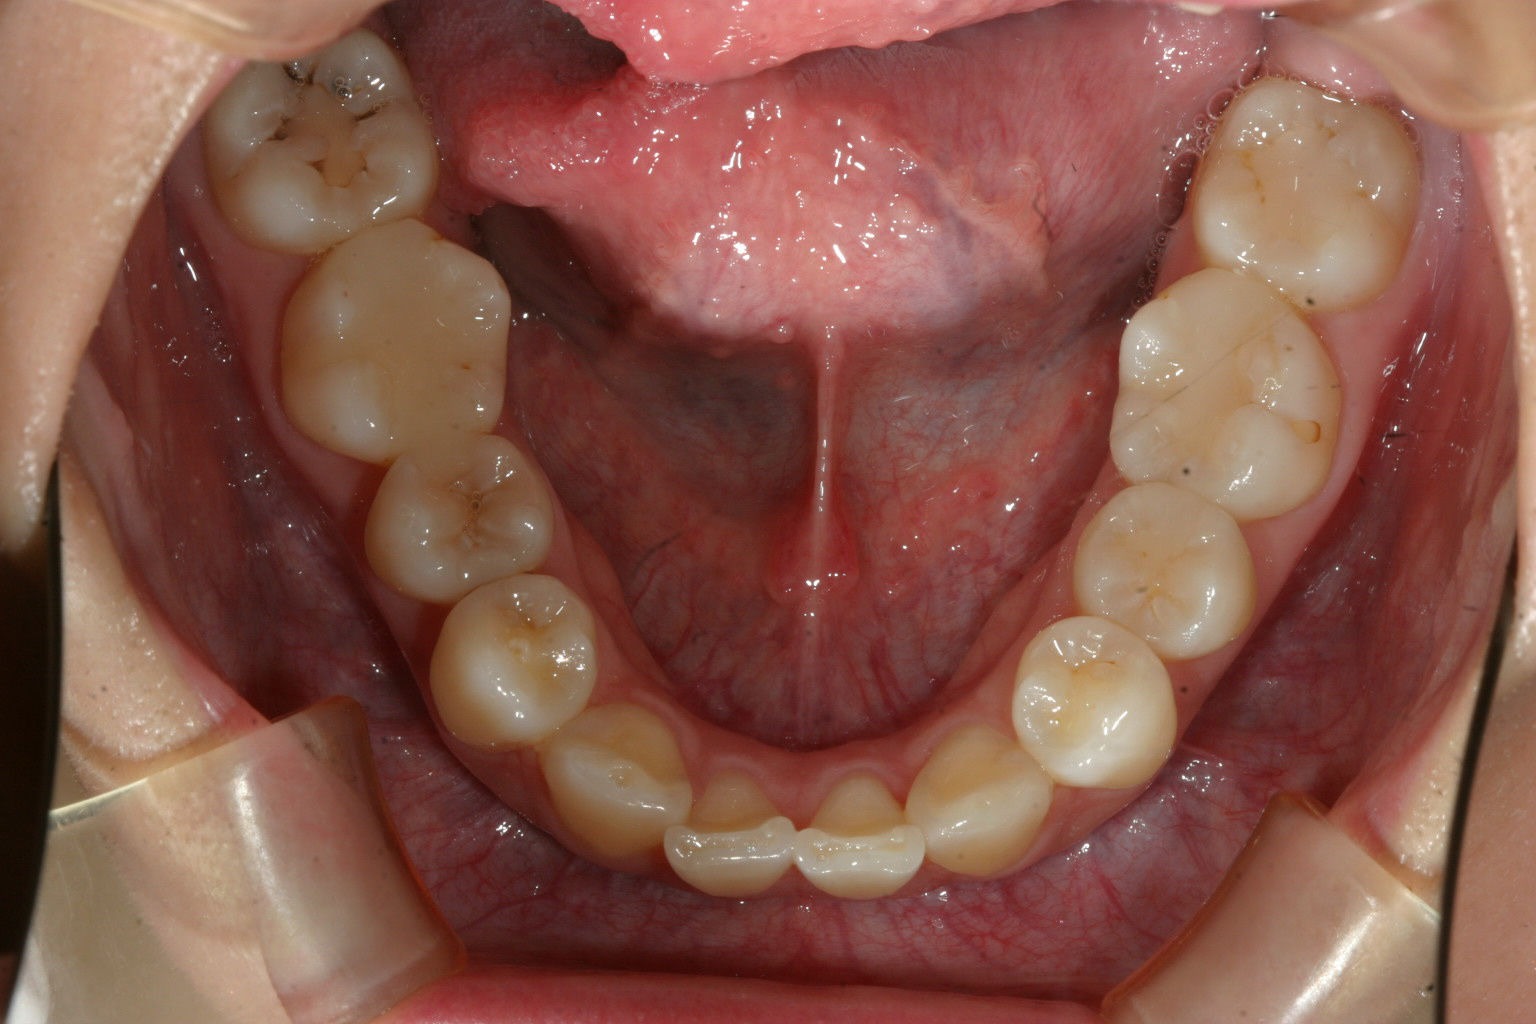

下顎は綺麗なもんです。

下顎は元々そんなにひどく無かったですから殆ど改善してます。